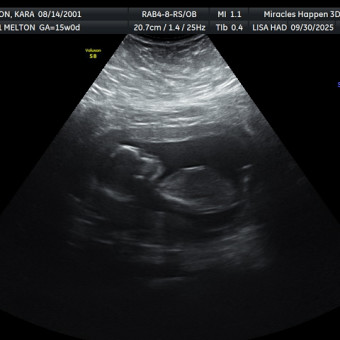

Kara & Blaine Melton

We cannot wait for our baby boy, Ridge, to arrive! Thank you for helping us celebrate our blessing.